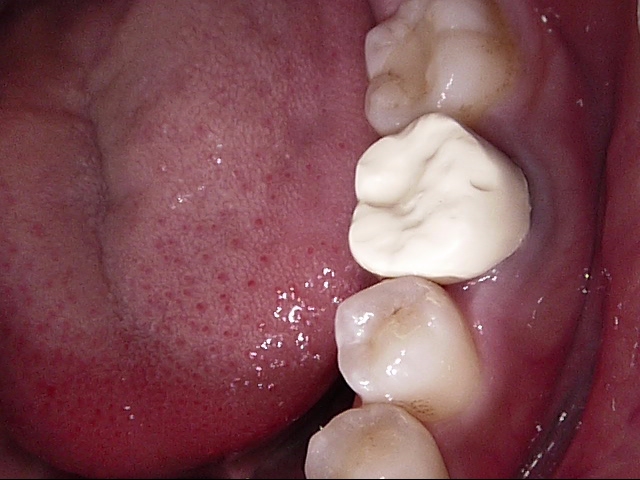

白い歯のなかでも保険適応のPEEK冠といって、割れにくい被せ物もあるのですが、色が真っ白になってしまうので、悪目立ちします。

PEEK冠の1例↓